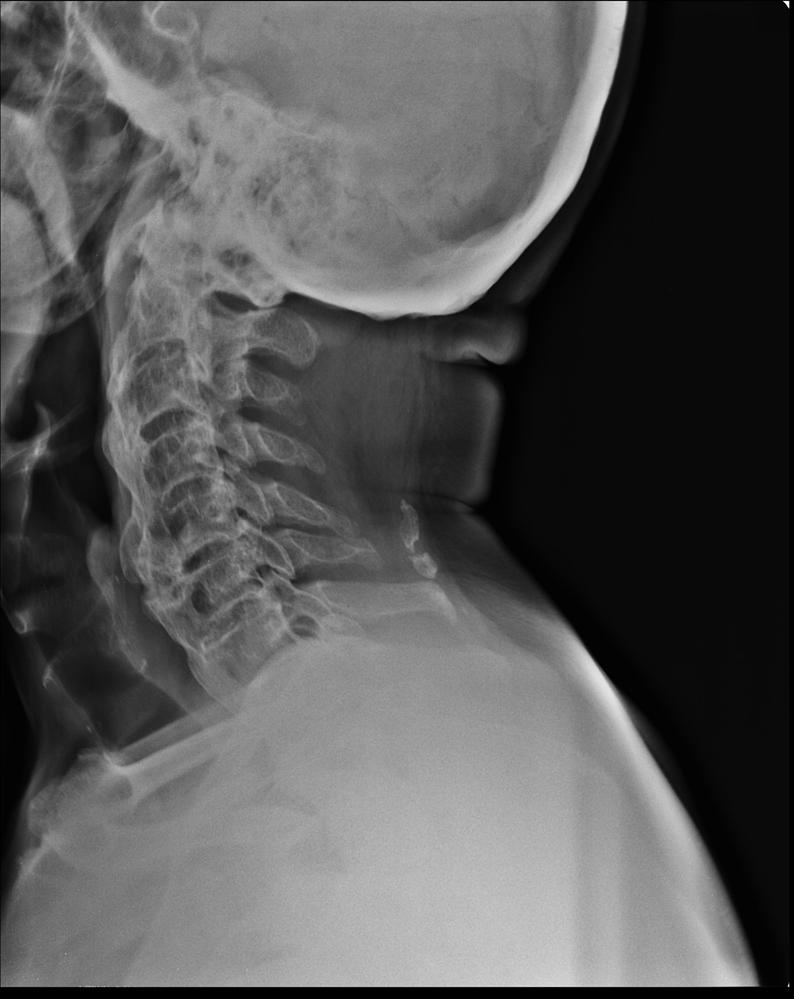

From www.thrivedc.org

C spine lat What Does Medical Term Dish Mean Diffuse idiopathic skeletal hyperostosis (dish) describes a phenomenon characterized by a tendency toward. Diffuse idiopathic skeletal hyperostosis (dish) is a form of arthritis that involves the tendons and ligaments around the spine. Dish, also known as forestier disease, is a common disorder of unknown etiology characterized by enthesopathy of the spine and extremities, that usually presents with back. Diffuse idiopathic. What Does Medical Term Dish Mean.

From www.learningradiology.com

LearningRadiology Diffuse, Idiopathic, Skeletal, Hyperostosis, DISH What Does Medical Term Dish Mean Dish, also known as forestier disease, is a common disorder of unknown etiology characterized by enthesopathy of the spine and extremities, that usually presents with back. Diffuse idiopathic skeletal hyperostosis (dish) is a type of arthritis that affects tendons and ligaments, mainly around your spine. Diffuse idiopathic skeletal hyperostosis (dish) is a form of arthritis that involves the tendons and. What Does Medical Term Dish Mean.